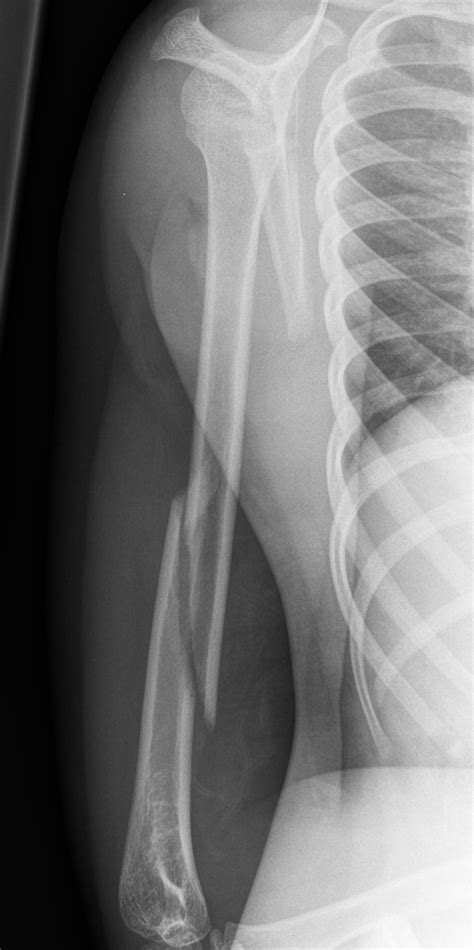

• X-rays: Imaging tests such as X-rays are used to visualize the bone and determine the type and severity of the fracture.

Humeral Shaft Fracture Affects the middle section of the humerus, often due to direct trauma.